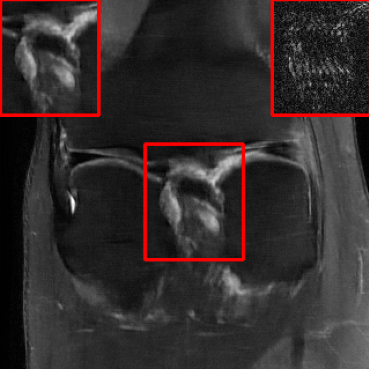

Results for the DIDN-based Reconstructor: To demonstrate adaptability to different network architectures, Table II compares reconstruction performance on the test set with the DIDN denoiser-based MoDL architecture. Average PSNR values with LONDN-MRI are compared to those with networks trained globally at different training set sizes. We ran only iteration of LONDN-MRI, where the reconstruction with a pre-trained (global) network was used to find neighbors. PSNR values for the oracle LONDN-MRI reconstructor are also shown. The overall performances with the DIDN-based architectures are better than with the UNet-based unrolled networks. The PSNRs for LONDN-MRI are consistently and similarly better than for the globally trained network across the different training set sizes considered, indicating potential for LONDN-MRI in improving state-of-the-art models. Fig. 6 visually compares reconstructions and reconstruction errors (in zoomed in region) for different methods. We can see that the LONDN reconstructors capture the original image features more sharply and accurately than the globally learned reconstruction.

| Ground Truth | Global | LONDN-MRI | Oracle |

| (1 iteration) | |||

![]() |

| PSNR = dB | PSNR = 34.15 dB | PSNR = 34.46 dB | PSNR = 34.54 dB |